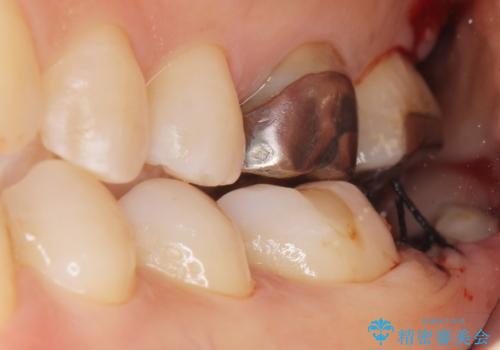

- 昔何回か根管治療した奥歯が膿んでいていて痛みがあることを主訴に来院された患者様です。

精査したところ、左下の奥歯にはひびが入っていて、保存不可能な状態でした。

義歯・インプラント・親知らずの移植の選択肢を提案したところ、移植をご希望されました。

割れている奥歯を抜去後左上の機能していない親知らずを移植し、生着したのち根管治療・補綴を行いました。